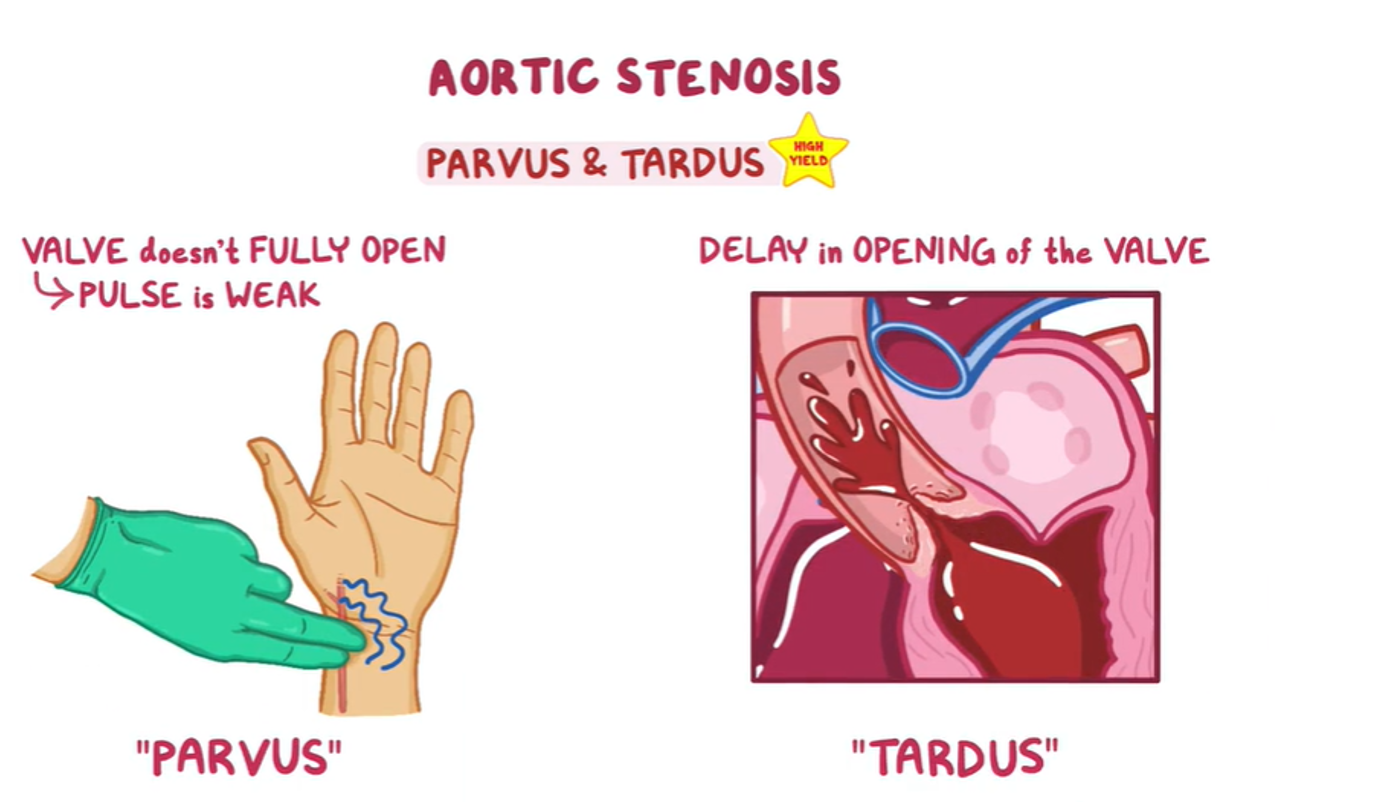

Examination Findings Z

- Weak & delayed distal pulse & decreased pulse amplitude.

- Narrow pulse pressure.